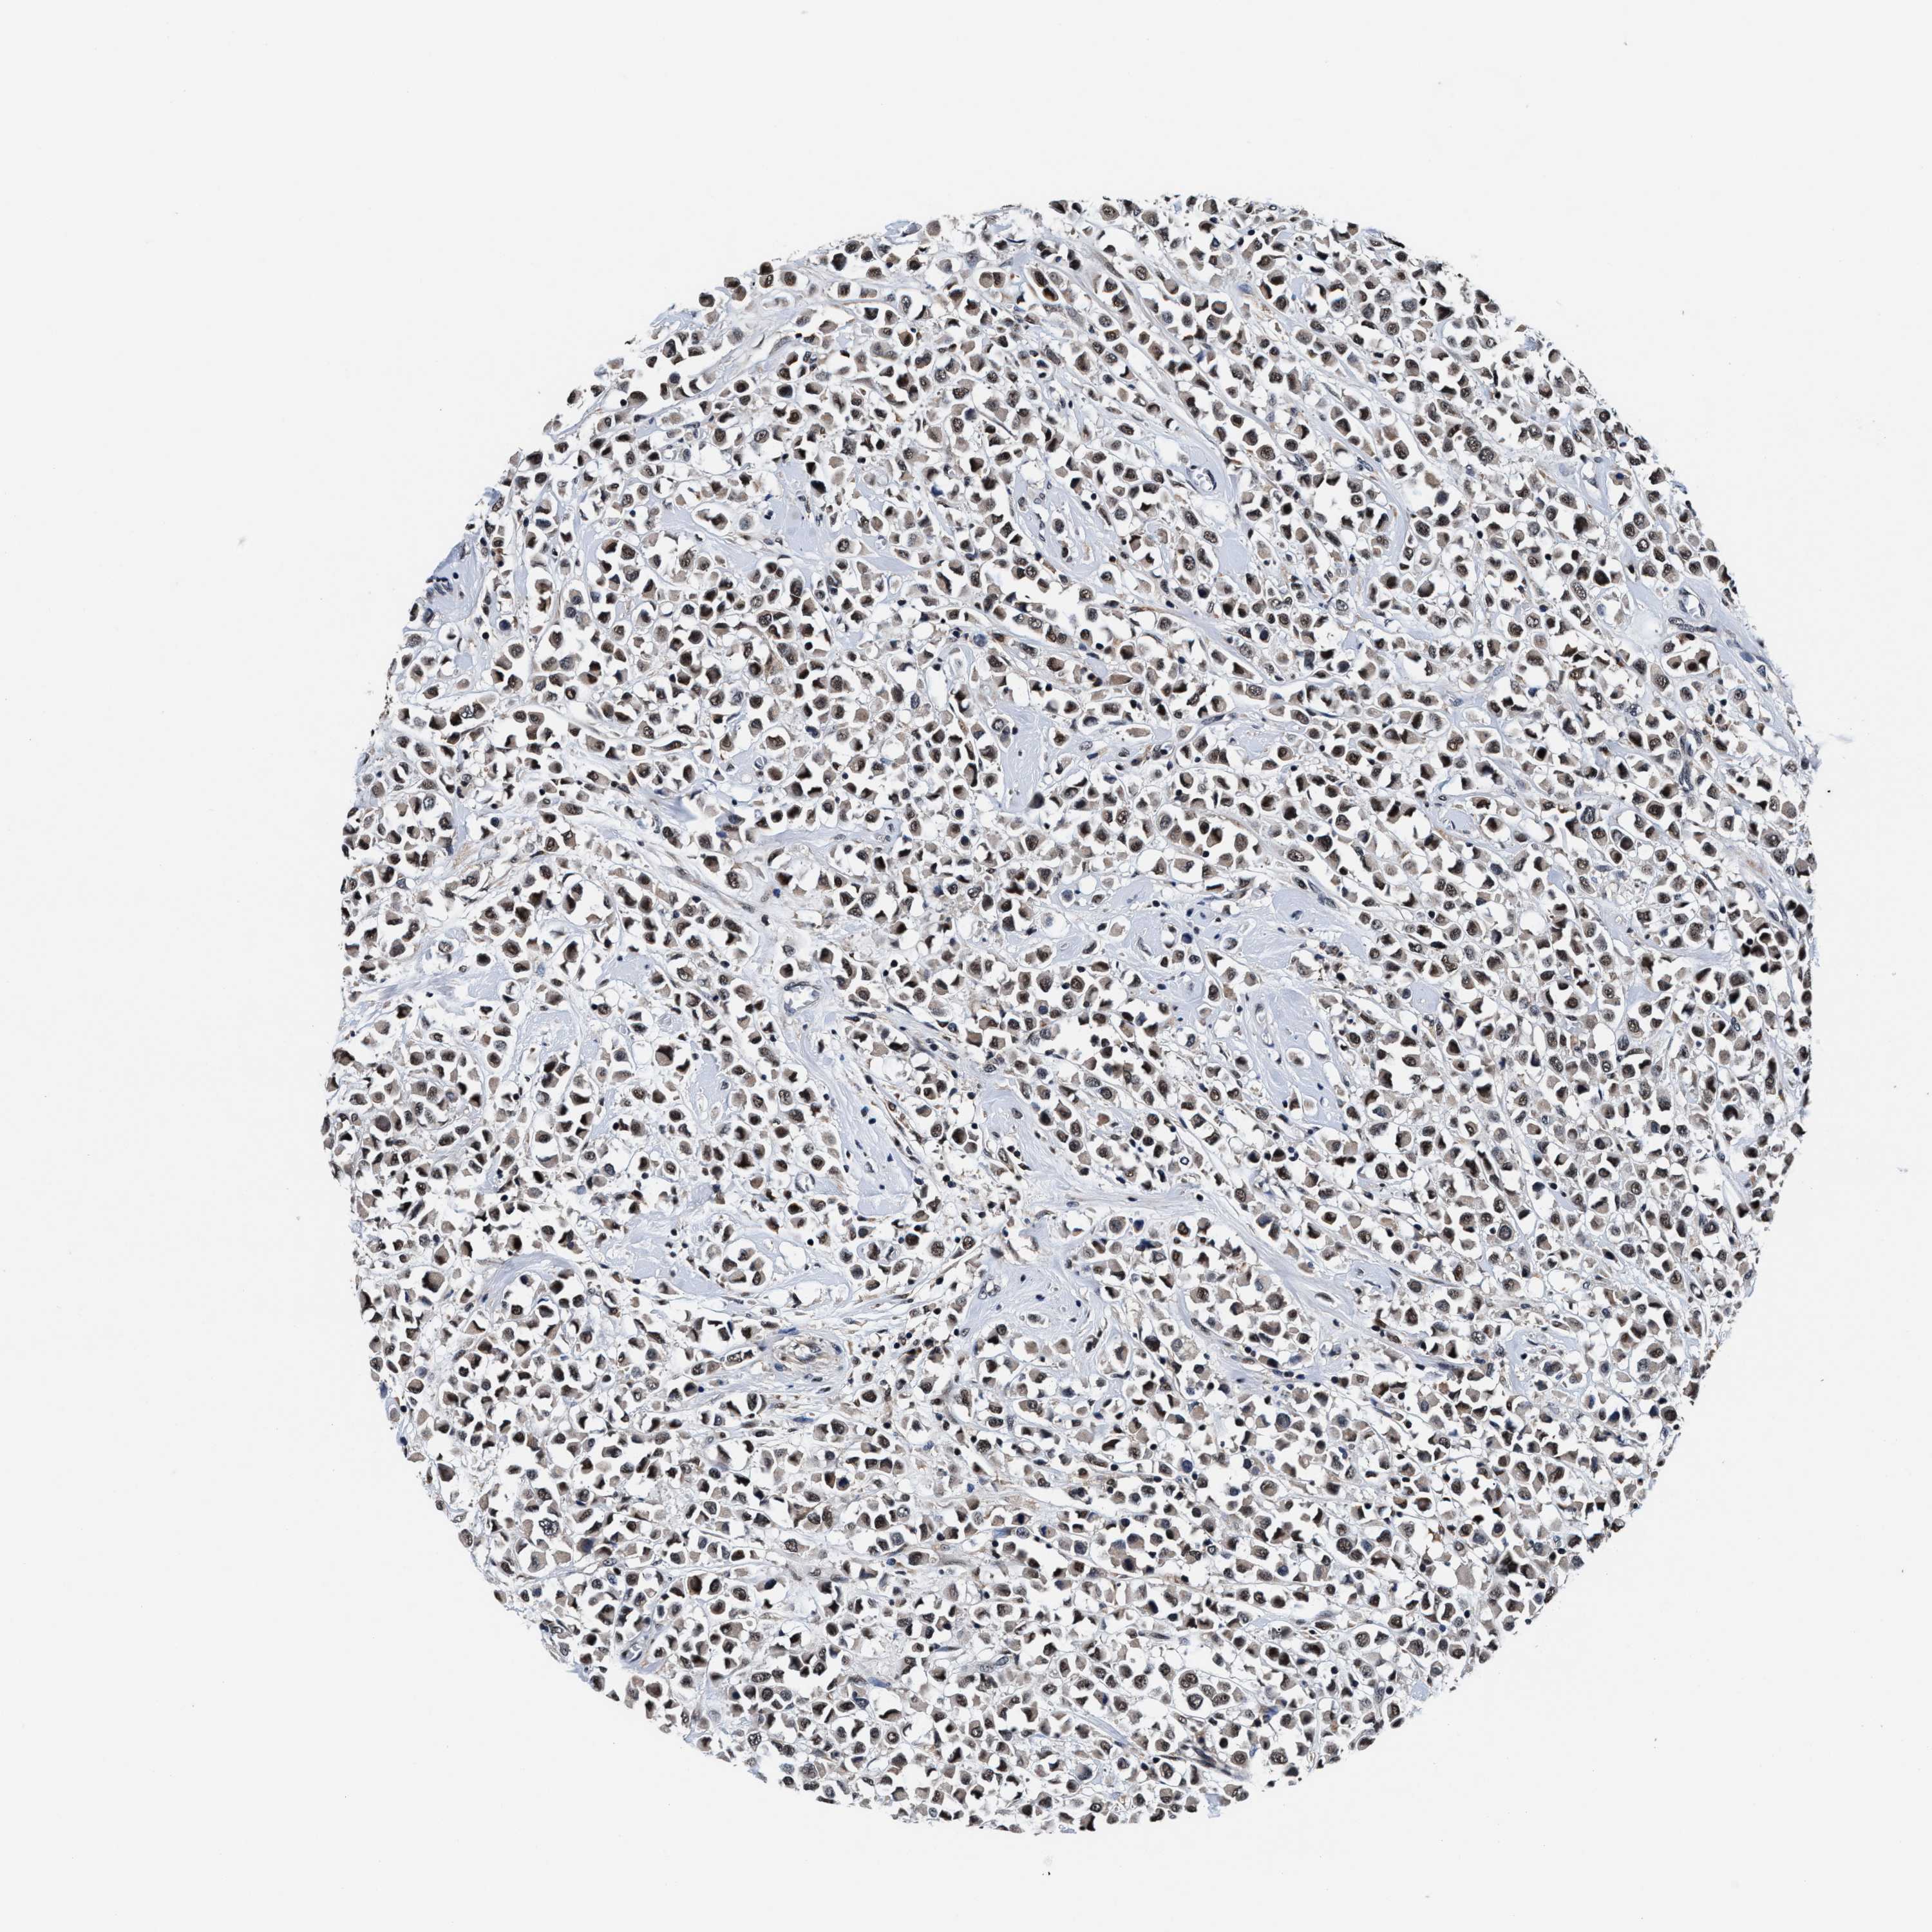

BRCA TCGA BRCA VALIDATION PROTEIN EXPRESSION

ANTIBODIES

AND

VALIDATION